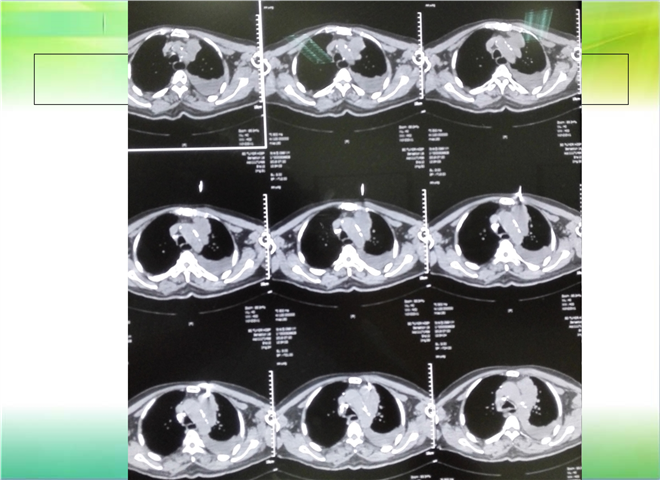

CT引导下穿刺活检术